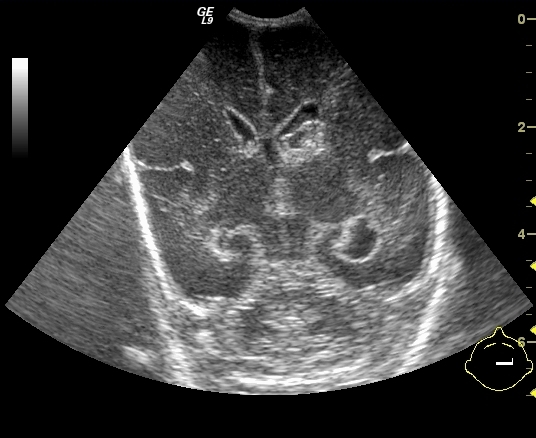

Cranial ultrasonography: is the first method of choice in brain parenchyma examinations. It can only be performed until the closure of the fontanelles (8-10months) (anterior and posterior fonatnelles, mastoidal and temporal region). Examinations require a high frequency convex transducer as well as a linear one. Vertebral ultrasound: can only be performed in the first 2-3 months of life until the closure of the vertebral arch, with a linear transducer.

30. a-d) Cranial ultrasound. Normal newborn brain. a-b. Coronal, c-d. Sagittal views.